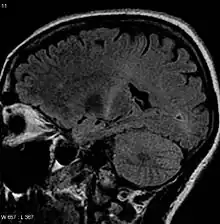

Because symptoms of ALS can be similar to those of a wide variety of other, more treatable diseases or disorders, appropriate tests must be conducted to exclude the possibility of other conditions. One of these tests is electromyography (EMG), a special recording technique that detects electrical activity in muscles. Certain EMG findings can support the diagnosis of ALS. Another common test measures nerve conduction velocity (NCV).[90] Specific abnormalities in the NCV results may suggest, for example, that the person has a form of peripheral neuropathy (damage to peripheral nerves) or myopathy (muscle disease) rather than ALS. While a magnetic resonance imaging (MRI) is often normal in people with early-stage ALS, it can reveal evidence of other problems that may be causing the symptoms, such as a spinal cord tumor, multiple sclerosis, a herniated disc in the neck, syringomyelia, or cervical spondylosis.[3]